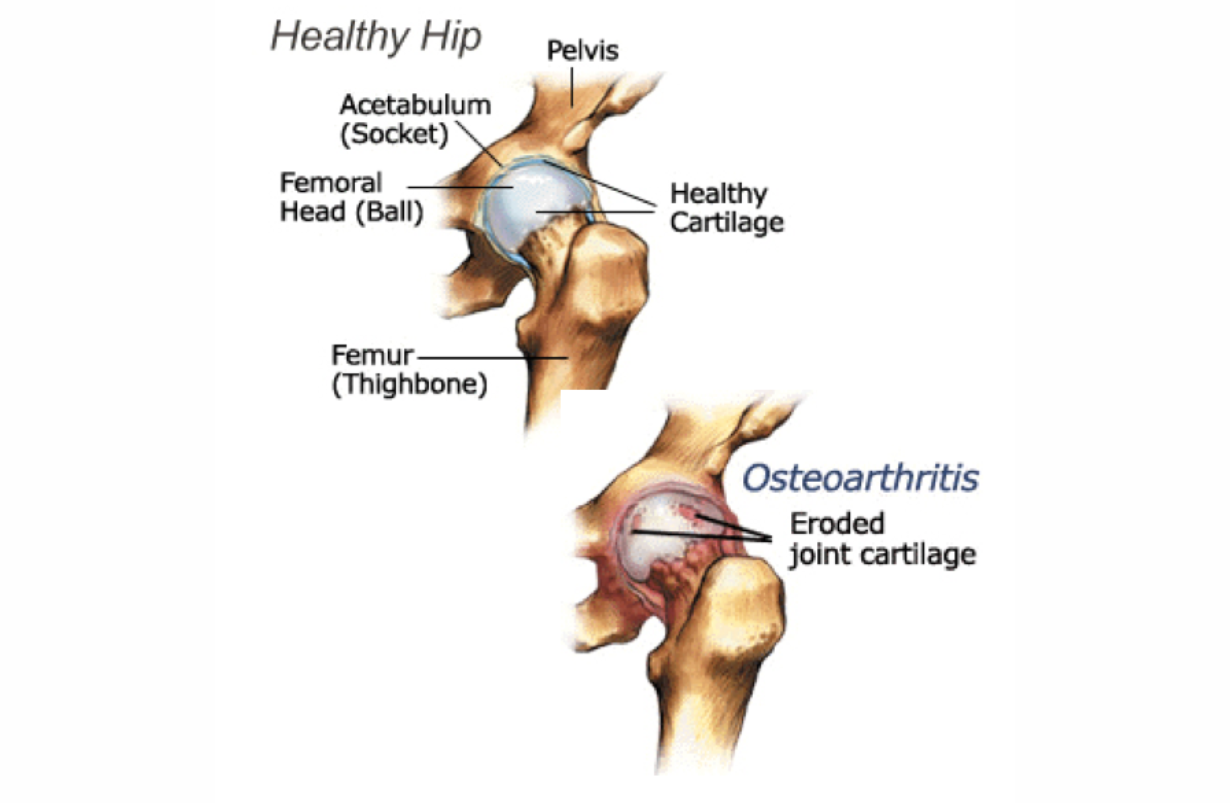

Arthritis Hip

Erosion of cartilage and dysfunctional reshaping of bones forming the hip joint.

Anterior Total Hip Replacement

Surgical insertion of metal and plastic artificial joint, in which the incision is made in the front or side of the hip. Few or no muscles are cut; recovery is brief and nearly complete. In a fair number of cases, final recovery has a greater range of motion than before surgery. After 3 months, a cautious re-beginning of yoga is almost always fine. If there is doubt, contact the orthopedic surgeon. The poses to avoid are those that abduct and extend the leg. Upavista Konasana, Baddha Konasana, and Virabhadrasana I, II and III are contraindicated for longer, but may be cautiously approached after 6 months.

Posterior Total Hip Replacement

Surgical insertion of metal and plastic artificial joint in which the incision is made in the back of the hip. Gluteal and piriformis muscles are cut; recovery is slower. Give the surgery three months to heal. The basic restrictions are on flexion, adduction and internal rotation, which can be remembered as "FAIR." These limitations will continue for all of life, although some increase of each of these ranges is possible: mild to moderate flexion (enough to sit comfortably) and some adduction (not quite up to the full Gomukhasana or Garudasana), and some adduction (caution re: Ardha Matsyendrasana III or Marichyasana). Full Paschimottanasana should be approached very carefully and slowly, and in some cases leads to malfunctioning of the prosthetic hip, even requiring replacement of it.